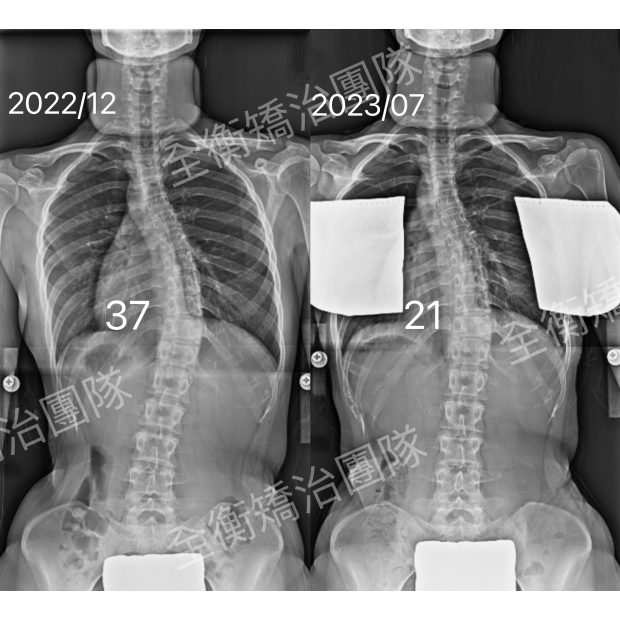

X光對比.jpg

24歲成年C型中度側彎女生,矯治7個月,度數減少43%

24歲的上班族女生,穿戴背架+復健運動7個月後

度數從37度進步至21度,減少了43%!

成人脊椎側彎只要是用對方法,還是有矯正減少度數的空間。